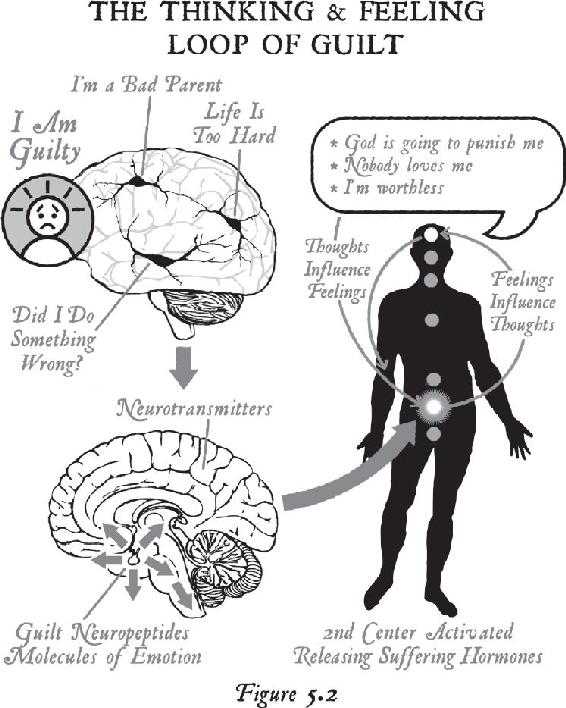

Because of our large brains, human beings are capable of thinking about their problems, reliving past events, or even forecasting future worst-case situations and thus turning on the cascade of stress chemicals by thought alone. We can knock our brains and bodies out of normal physiology just by thinking about an all-too-familiar past or trying to control an unpredictable future.

Every day, Anna relived that event over and over in her mind. What she didn’t realize was that her body did not know the difference between the original event that created the stress response and the memory of the event, which created the same emotions as the real-life experience all over again. Anna was producing the same chemistry in her brain and body as if the event were actually happening again and again. Subsequently, her brain was continuously wiring the event into her memory bank, and her body was emotionally experiencing the same chemicals from the past at least a hundred times each day. By repeatedly recalling the experience, she was unintentionally anchoring her brain and body to the past.

Emotions are the chemical consequences (or feedback) of past experiences. As our senses record incoming information from the environment, clusters of neurons organize into networks. When they freeze into a pattern, the brain makes a chemical that is then sent throughout the body. That chemical is called an emotion. We remember events better when we can remember how they feel. The stronger the emotional quotient from any event—either good or bad—the stronger the change in our internal chemistry. When we notice a significant change inside of us, the brain pays attention to whoever or whatever is causing the change outside of us—and it takes a snapshot of the outer experience. That’s called a memory.

Therefore, the memory of an event can become branded neurologically in the brain, and that scene becomes frozen in time in our gray matter, just as it did for Anna. The combination of various people or objects at a particular time and place from that stressful experience is etched in our neural architecture as a holographic image. That’s how we create a long-term memory. Therefore, the experience becomes imprinted in the neural circuitry, and the emotion is stored in the body—and that’s how our past becomes our biology. In other words, when we experience a traumatic event, we tend to think neurologically within the circuitry of that experience and we tend to feel chemically within the boundaries of the emotions from the event, so our entire state of being—how we think and how we feel—becomes biologically stuck in the past.

As you can imagine, Anna was feeling a rush of negative emotions: tremendous sadness, pain, victimization, grief, guilt, shame, despair, anger, hatred, frustration, resentment, shock, fear, anxiety, worry, overwhelm, anguish, hopelessness, powerlessness, isolation, loneliness, disbelief, and betrayal. And none of those emotions dissipated quickly. As Anna analyzed her life within the emotions of the past, she kept suffering more and more. Because she couldn’t think greater than how she constantly felt, and since emotions are a record of the past, she was thinking in the past—and every day she felt worse. As a psychotherapist, she could rationally and intellectually understand what was happening to her, but all her insights couldn’t get beyond her suffering.

People in her life started treating her as the person who had lost her husband, and that became her new identity. She associated her memories and feelings with the reason she was in her present state. When anyone asked her why she felt so bad, she told the story of the suicide—each time reliving the pain, anguish, and suffering over again. All along, Anna kept firing the same circuits in her brain and reproducing the same emotions, conditioning her brain and body further into the past. Every day, she was thinking, acting, and feeling as if the past were still alive. And since how we think, how we act, and how we feel is our personality, Anna’s personality was completely created by the past. From a biological standpoint, in repeatedly telling the narrative of her husband’s suicide, Anna literally couldn’t get beyond what had happened.

It’s amazing how this can happen to so many people. Because of a shock or trauma in their lives, they never get beyond those corresponding emotions, and their health and their lives break down. If an addiction is something that you think you can’t stop, then objectively it looks as though people like Anna become addicted to the very emotions of stress that are making them sick. The rush of adrenaline and the rest of the stress hormones arouses their brain and body, providing a rush of energy.1 In time, they become addicted to the rush of that chemistry—and then they use the people and conditions in their lives to reaffirm their addiction to the emotion, just to keep feeling that heightened state. Anna was using her stressful conditions to re-create that rush of energy, and without realizing it, she became emotionally addicted to a life she hated. Science tells us that such chronic, long-term stress pushes the genetic buttons that create disease. So if Anna was turning the stress response on by thinking about her problems and her past, her thoughts were making her sick. And since stress hormones are so powerful, she had become addicted to her own thoughts that were making her feel so bad.